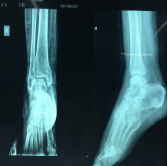

手法整复桡骨远端骨折、踝关节骨折、尺骨骨折、掌骨骨折、指骨骨折、跖骨骨折及肩关节脱位、桡骨小头半脱位等各类骨折脱位十余例,行小夹板固定及石膏托外固定十余例。